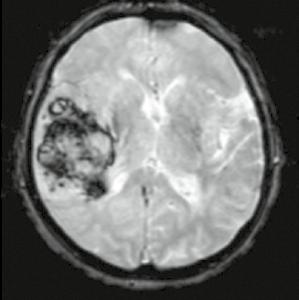

Osmdesátiletá pacientka, z kardiologických důvodů dlouhodobě na warfarinu, hypertonička. Náhlé bezvědomí, pád z postele. Při přijetí somnolentní, jednoduchým výzvám vyhoví, hlavu a bulby stáčí doprava, levostrannými končetinami hůře pohybuje. Zemřela 5. den po mozkové příhodě.

Obr. A2.1–A2.4 Intracerebrální krvácení v akutním stadiu (1. den), oxyhemoglobin, ale již příměs deoxyhemoglobinu